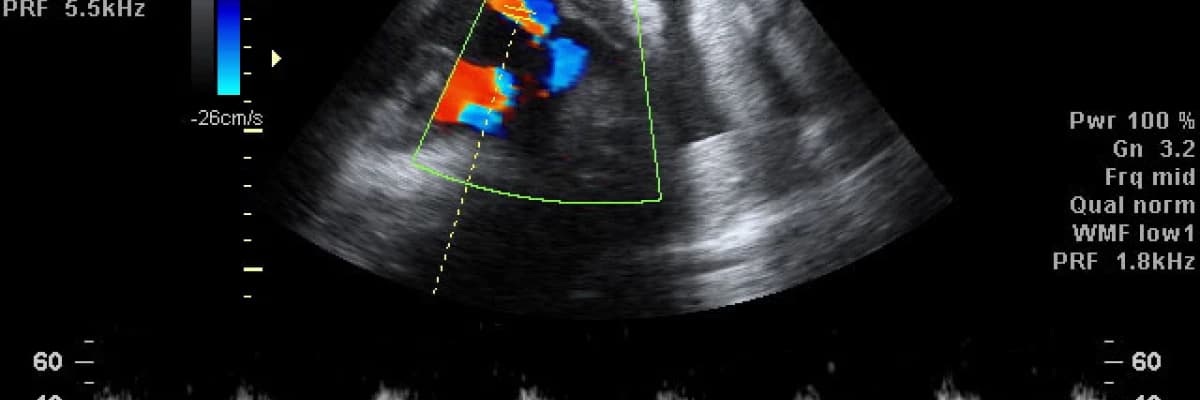

Doppler genel anlamda ultrason altında incelenen damar yatağının kan akımını ve normal dışı bir dirençle karşı karşıya olup olmadığını belirleyen bir testtir. Halk arasında ‘’renkli ultrason’’ olarak bilinen ultrason çeşidi budur ve amaç bebeği renkli olarak görüntülemek değil kalbin sistol (atım) ve diyastol (dolum) zamanlarında “kan akım hızlarını” incelemektir.

Gebeye yapılan rutin ultrason incelemesinden sonra önce sağlı sollu uterin arterlerde, sonra da umbilikal (kordon) arterde doppler incelemesi yapılır. Her iki uterin arterin akım değerleri, ikisi arasındaki matematiksel fark ve görünüm şekilleri değerlendirilir. Umbilikal arterde de yine akım değerlendirilir ve dalga şekli incelenir.

Doppler tanı koydurucu değil yönlendirici bir testtir. Patolojik akım değerleri ya da anormal dalga görünümleri elde edildiğinde bebeğin diğer iyilik hali testleriyle yakından değerlendirilmesi konusunda hassas olunması gerektiğini gösterir. Bunun tek istisnası umbilikal arterde "ters akım" denen bir durumun ortaya çıkmasıdır. Umbilikal arterde bu anormal dalga şekli gözlendiğinde bebeğin karında ölme riski oldukça yüksektir ve acil doğum gerekebilir.

İntrauterin gelişme geriliği olan bebeklerde hem ölüm, hem de doğum sırasında hipoksi ve metabolik asidoz riski mevcuttur. Bu nedenle anne karnındaki bebeğin büyümesinin ve iyilik halinin çok yakından takip edilmesi gereklidir. Uygun doğum zamanının belirlenmesinde gestasyonel yaş (gebelik haftası) ve bebeğin durumu çok önemlidir. Termde yada terme (miyad) yakın olan bebeklerde doğum kararı rahatlıkla verilmelidir. Asıl sorun hamilelik haftası çok küçük olan bebeklerdir. Bu bebekler için biyofizik profil testi (BPP), amnion sıvı miktarı, NST ve fetal damarların Doppler ultrasonografisi gibi çeşitli takip yöntemleri kullanılır. Her ne kadar normal amniyon sıvı hacmi rahim içi gelişme geriliğinin olmadığını gösteremese de, sıvının az olması (oligohidramnios) büyük olasılıkla intrauterin gelişme geriliğini olduğunu düşündürür.

Termde ya da terme yakın olan rahim içi gelişme gerilikli bebeklerde doğum kararı verilme nedenleri: annenin tansiyonlarının yüksek seyretmesi, bebeğin büyümesinde 2 ila 4 haftalık bir duraklamanın olması, biyofizik profil (BPP) skorunun 6’dan düşük olması yada Doppler ultrason ölçümlerinde diyastol sonu akım kaybı olmasıdır.

Termden uzakta olan, gebelik haftası küçük bebekler için Doppler ultrason ölçümlerinin normal olması güven vericidir.